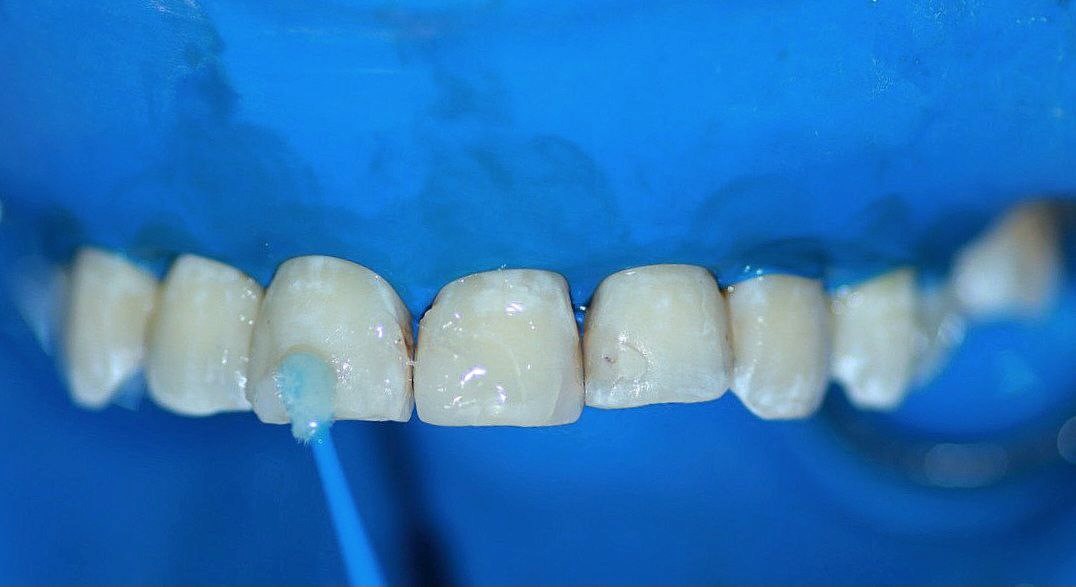

Se realizaron tres aplicaciones a intervalos de 60 segundos, eliminando el producto con una torunda de algodón entre cada una de ellas. Tras lo cual fue colocada una disolución saturada de bicarbonato de sodio con agua para neutralizar el ácido (figura 3).

Figura 3. Tras un periodo de espera de un minuto, se retiró el producto con una torunda de algodón y se realizó enjuague con agua